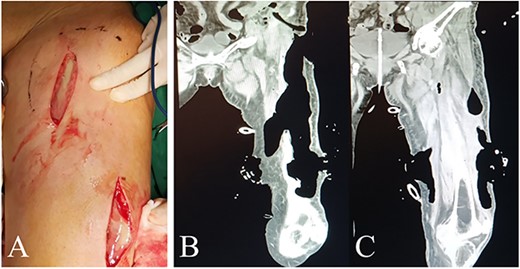

Intraoperative view of left thigh in the second and third operation. Lateral view of left thigh before (A) and after (B) removing VSD (PU) material in the second operation. (C) Anterior view of left thigh after removing VSD (PU) material in the third operation. (D) Interior and (E) lateral view of repaired left thigh.

Postoperative findings of laboratory examination improved significantly. The patient spent several days in residential care in surgical ward with nutritional support. Bacterial culture of pus extracted in the first surgery was negative. On hospital day 12, a second surgery was performed to remove VSD (PU) material, finding a large amount of remaining necrotic fascia and part of the pus cavity not completely cleared. After thorough debridement, the left thigh and the posterior peritoneal pus space were treated with VSD and filled with PU again. Significant improvement were observed in symptoms and laboratory findings, so meropenem was discontinued and downgraded to amoxicillin on day 16. In the third surgery on day 19, distinct fresh wounds without necrotic tissue were observed. The drainage tubes were placed in multiple places to fully drain the potential remnant cavity in the thigh. Multipoint skins were sewn and fixed, and then received pressure dressing with self-adhesive elastic bandage. The abdominal drainage tube was retained and kept unobstructed for subsequent tumor surgery.